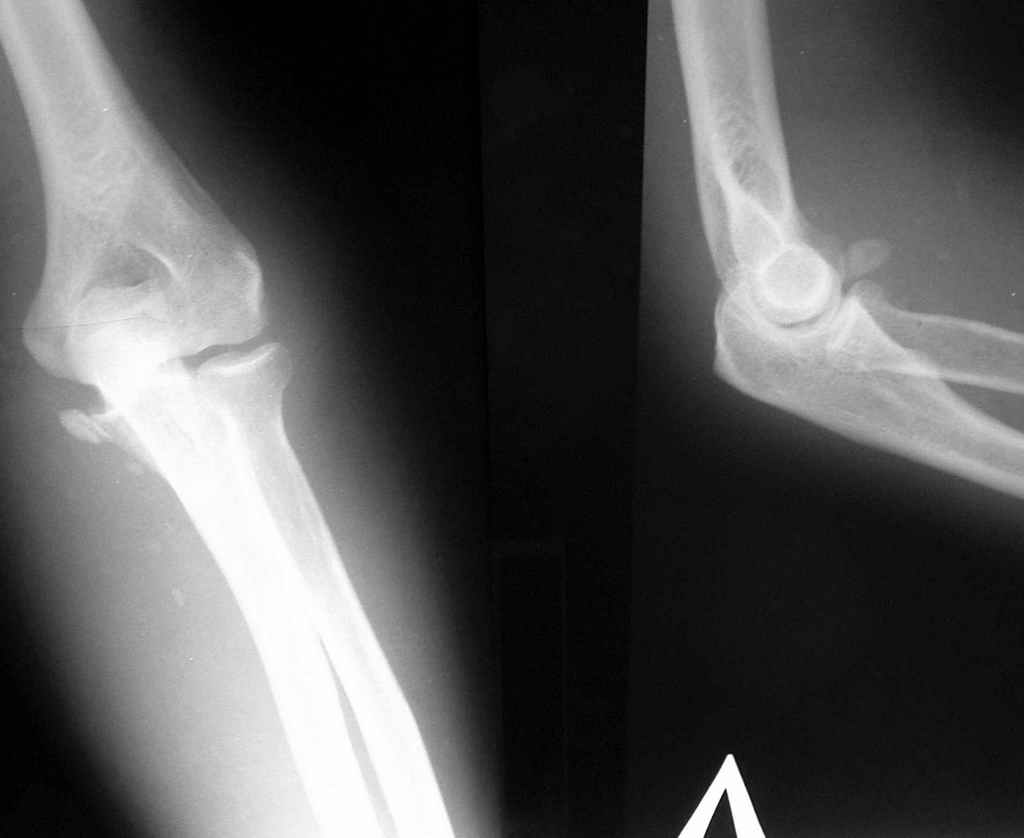

Уважаемые коллеги, 49-летний мужчина во время армреслинга получил травму локтевого сустава.

3 недели лечился в травмпункте с диагнозом отрывной перелом медиального надмыщелка левой плечевой кости (Rtg-1). Лечение состояло в ношении руки на косыночной повязке. Затем в другом учреждении сделали КТ (рис 2,3,4).

Неврологии нет, выраженный отек, активные движения в объеме 60 градусов. Сейчас прошло 4 недели после травмы.

Что же все-таки сломано? Что бы Вы сделали (или не стали бы делать)?